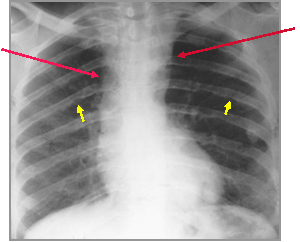

Convexity

above aortic

knob due to

dilated LSCA

or Aorta

proximal to

coarct

Ascending

Ao may be

dilated,

normal or

small

Coarctation of the Aorta